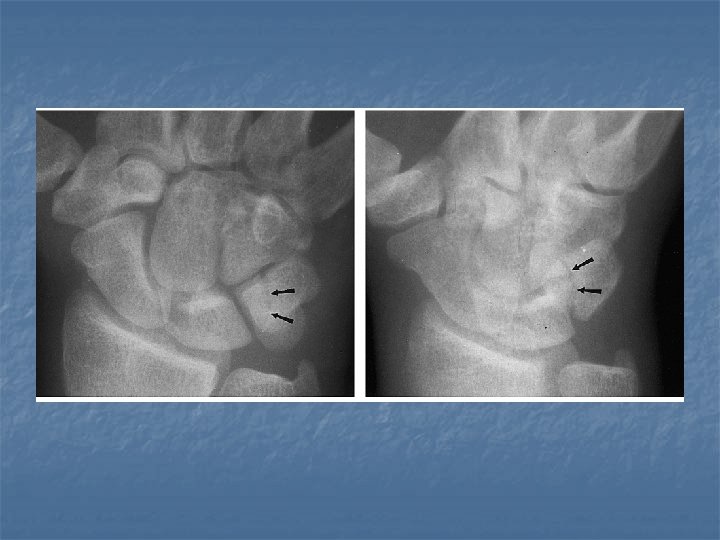

Fracture of triquetral n n Usually a subtle fracture Best seen in the lateral or pronated oblique view.